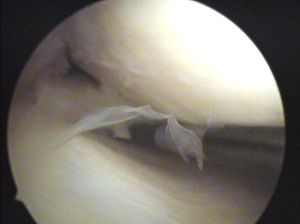

Ich zeig Ihnen mal einen Blick ins Knie:

Sie sehen den Innenmeniskus, wie er gerade mit Hilfe eines Hakens nach vorne gezurrt wird. Nicht schlimm, oder?

(mich erinnert´s irgendwie an Nudeln)